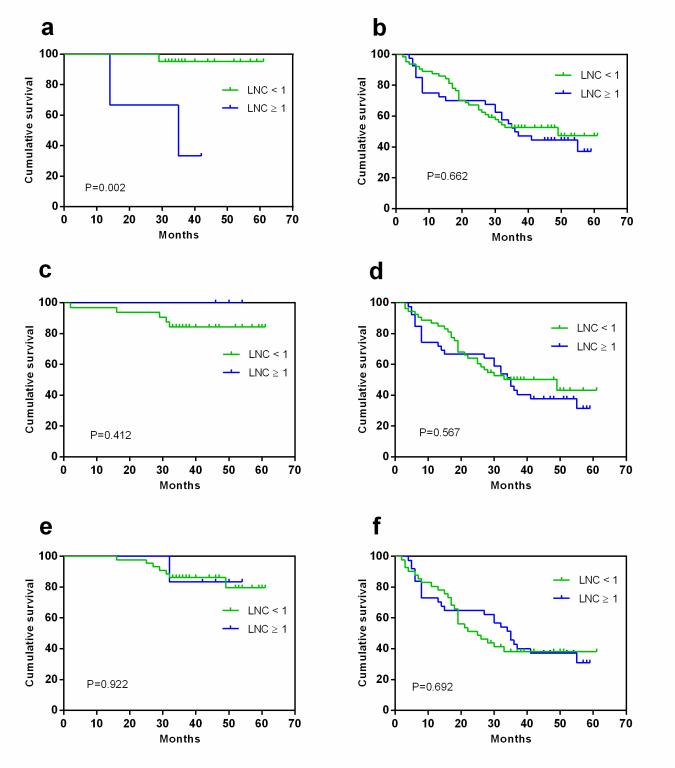

MDCT 淋巴结数目对胃腺癌切除术后的总体生存的影响依据计数标准及 TNM分期不同而不同���。对于 T1-2 的胃癌患者���,预后的评估更应警惕 8mm 以上的 MDCT淋巴结数目���。而对于相对进展期的 T3-4, N+, 与 III 期的胃癌患者��,推荐较小的大小(5mm)作为标准以 MDCT 淋巴结数目对胃癌患者进行预后评估����。

图3 依据于TNM分期��,MDCT淋巴结数目对胃癌总体生存的影响(8mm为阈值)